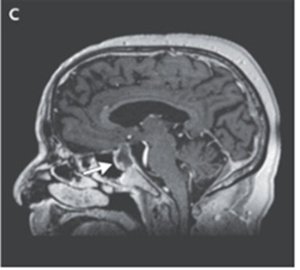

頭部MRIではT1強調像にて出血を伴う下垂体病変の拡大が明らかになった。

「下垂体卒中」と診断された。

ヒドロコルチゾンを静脈内投与して、経鼻的巨大腺腫切除術が施行された。

処置後4日目に、患者の視力はベースラインに戻り、後療法としてPSLとチラーヂンSの内服継続がなされることとなった。3か月後のフォローアップ外来では、右眼球運動麻痺は認めなくなっていた。